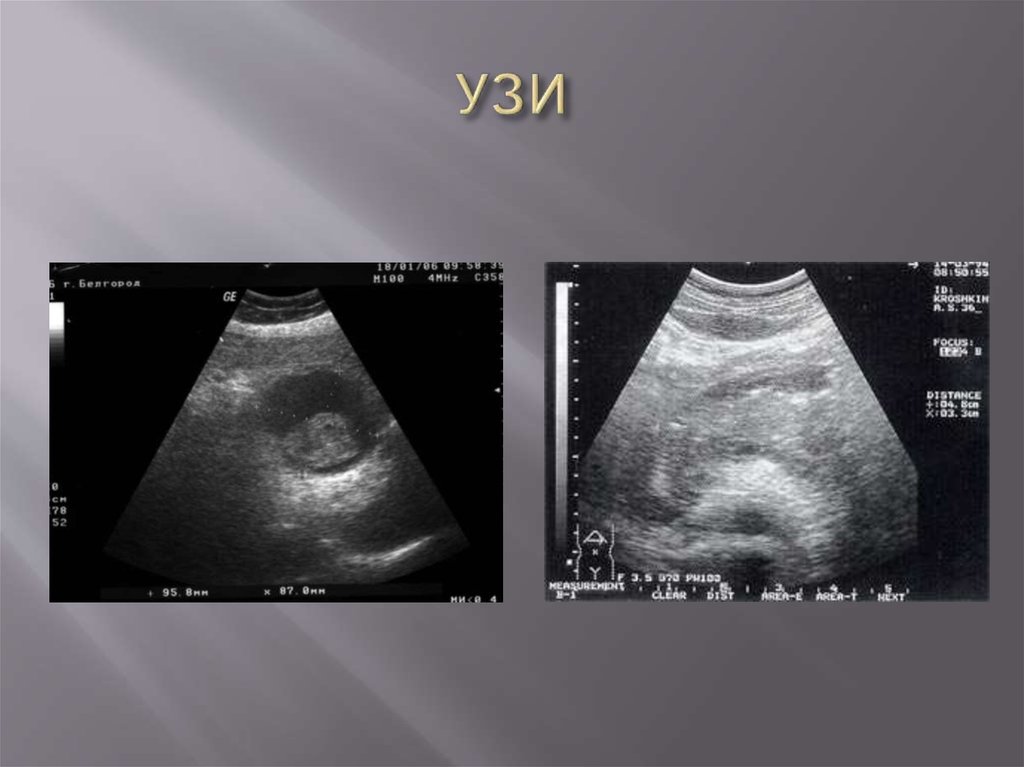

УЗИ

Амилазы и липазы в сыворотке

Амилазы и липазы в сыворотке (гайдлайн)

Диагностика